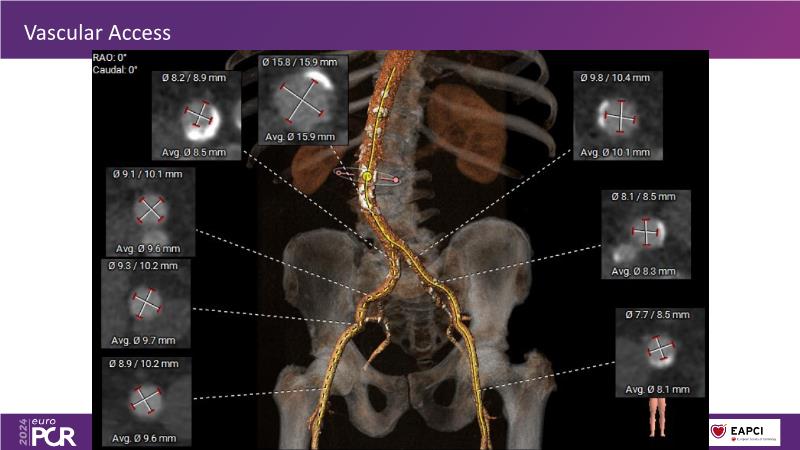

In this session, explore the next-generation balloon-expandable Myval Octacor THV, focusing on its key features, procedural impact, and potential clinical benefits. Understand the procedural steps for planning and implanting it, especially for intermediate and extra-large sizes, using the Octalign technique. Learn about the unmet clinical need of considering TAVI in extra-large annuli, and the clinical significance and relevance of Myval Octacor THV XL sizes. Gain insights from experts on best-in-class TAVI practices, including pre-procedural imaging, sizing rationale, treatment strategies, procedural tips and tricks, and post-procedural management. Additionally, review the latest outcomes from the LANDMARK pivotal RCT and other clinical evidence to date.

- To learn from the experts best-in-the-class TAVI practice: pre-procedural (imaging, sizing rationale, treatment strategy), procedural tips & tricks and post-procedural management